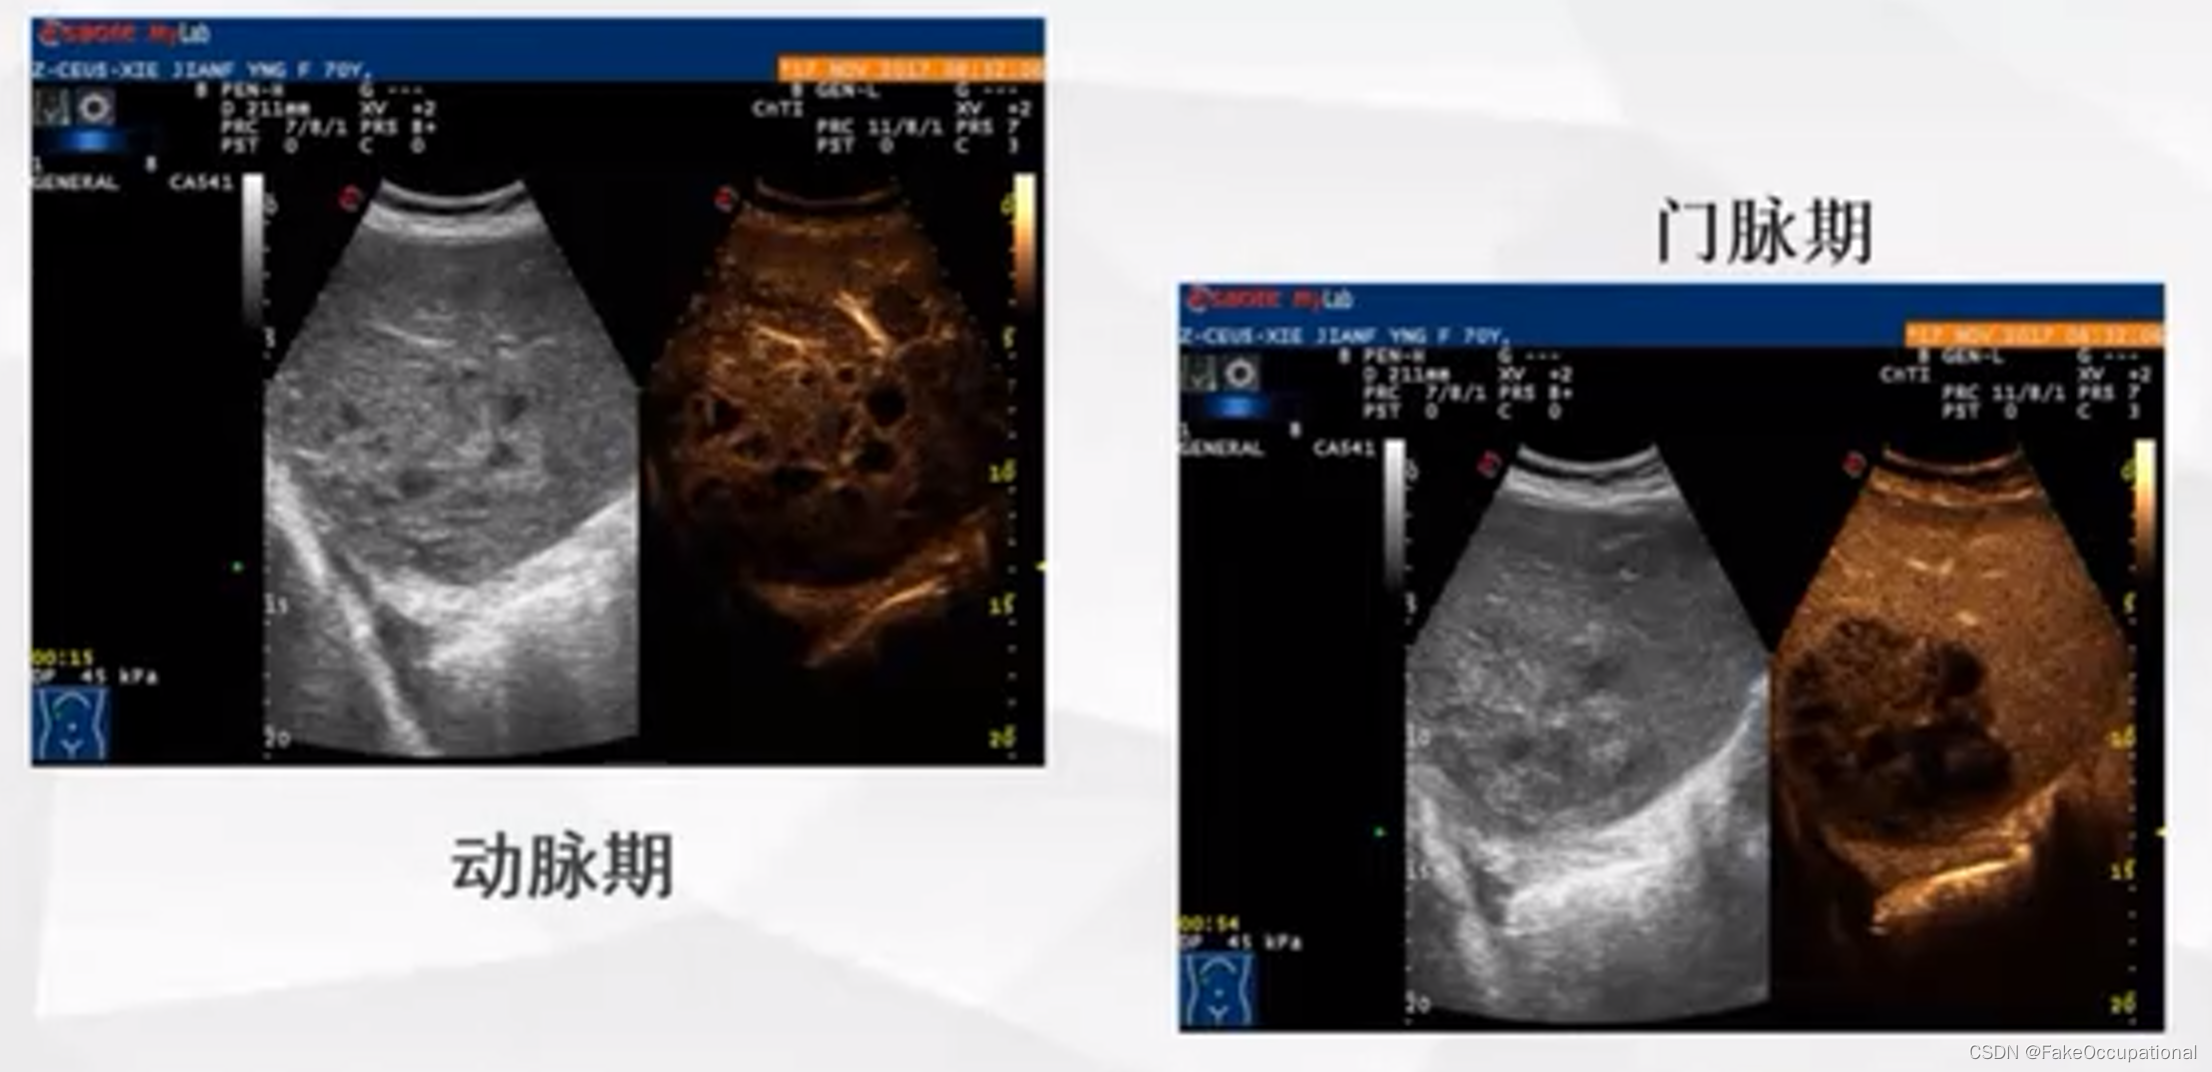

异常肝脏超声表现